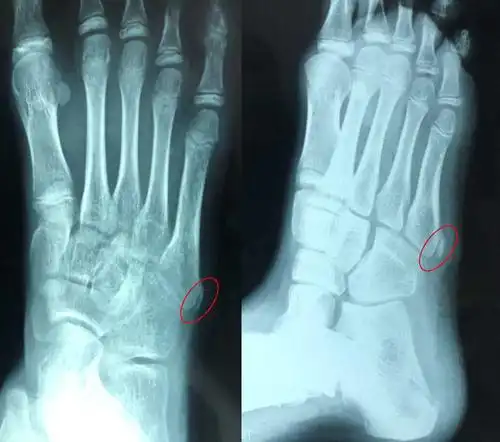

莫名其妙的孩子的脚居然多长了一块骨头!"婷婷也没有受过伤啊!

7岁小孩的脚这块骨头突出正常吗?